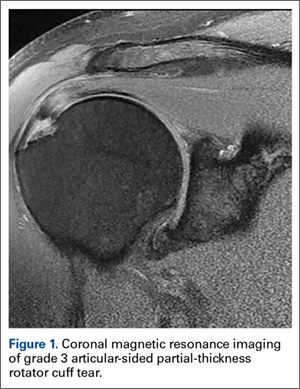

Figure 1: Rotator Cuff Tear This rotator cuff tear is seen in the The muscle is lit up in bright white and you can see a dark spot indicating the Figure 2: Partial Rupture This is a partial rupture of one of the rotator cuff The red arrow indicates the rupture Figure 3: Complete Rotator Cuff Tear